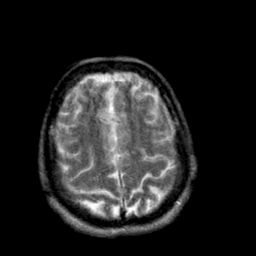

Creutzfeld-Jakob disease: T2-weighted MR -- Slice #18

[Home][Help][Clinical] Slice 18